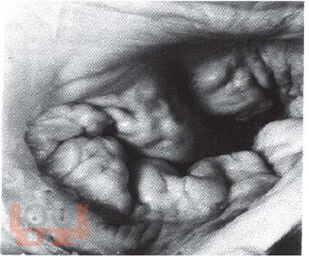

В книге подробно изложены этиология, клиника, дифференциальная диагностика и вопросы лечения пролапса митрального клапана у детей. Приводятся клинические варианты пролабирования в зависимости от тяжести соединительнотканной дисплазии и миксоматозной дегенерации.